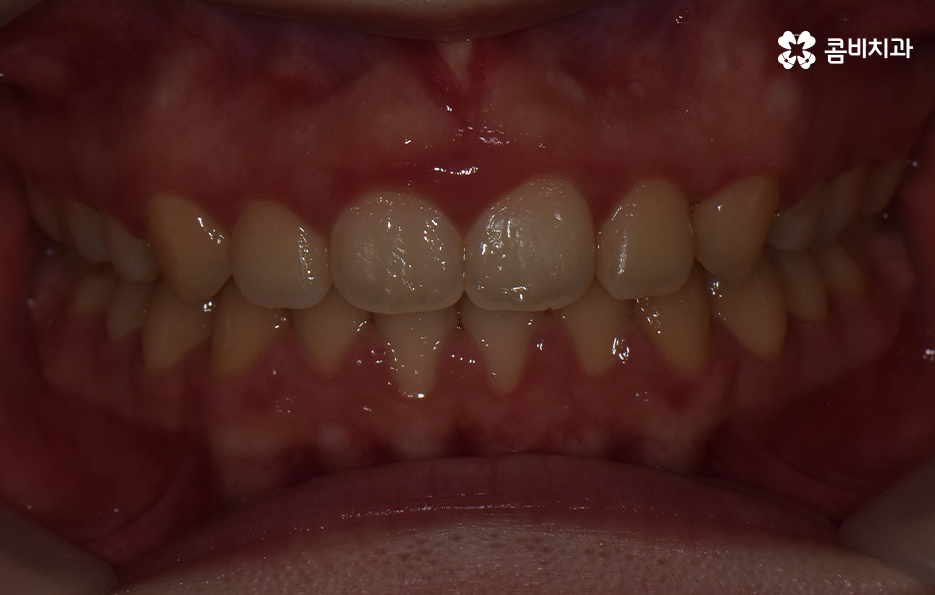

많은 분들이 치아 벌어짐을 해결하기 위해 라미네이트나 교정 등 다양한 치료법에 대해 비교해보고 고민하고 있는데요. 오늘은 치아 사이 벌어짐을 교정을 통해 해결하고 앞니의 돌출도 개선한 사례를 알아볼 거예요

아랫니의 경우 치아 사이가 벌어져 있기 때문에 치아를 이동시킬 수 있는 공간이 이미 확보된 상태이고 윗니는 다소 돌출된 앞니를 안쪽으로 들어오게 하면서 심미선을 얼굴형에 조화롭게 맞출 수 있으며 그와 동시에 윗니와 아랫니의 교합도 고려한 치료 계획을 세운 것으로 간단하게 말씀드릴 수 있어요

그리고 치열 뿐 아니라 얼굴형과의 조화도 고려해야 하기 때문에 단지 가지런한 치열이 아니라 자신의 얼굴과 자연스럽게 어울리면서 건강한 치아를 목표로 치료 계획을 세우시길 바라고 있는데요.

살다보면 치아가 깨지거나 충치로 인해 치아가 벌어지는 경우도 있고 왜소치로 인해 치아가 벌어진 경우도 있기 때문에 무조건 교정이 답이라고 말씀드리긴 어렵지만 치아는 평생 관리해야 한다는 점에서 자연치아를 되도록 보존하고 살리면서 아름다움을 추구하는 것을 기본으로 권하고 있다는 것을 다시 한번 강조드리며 치료 계획의 정확성을 위해 치과에서 자신이 원하는 치료 목표를 치과의사와 먼저 잘 상의해보시고 결정하시길 바라고 있어요